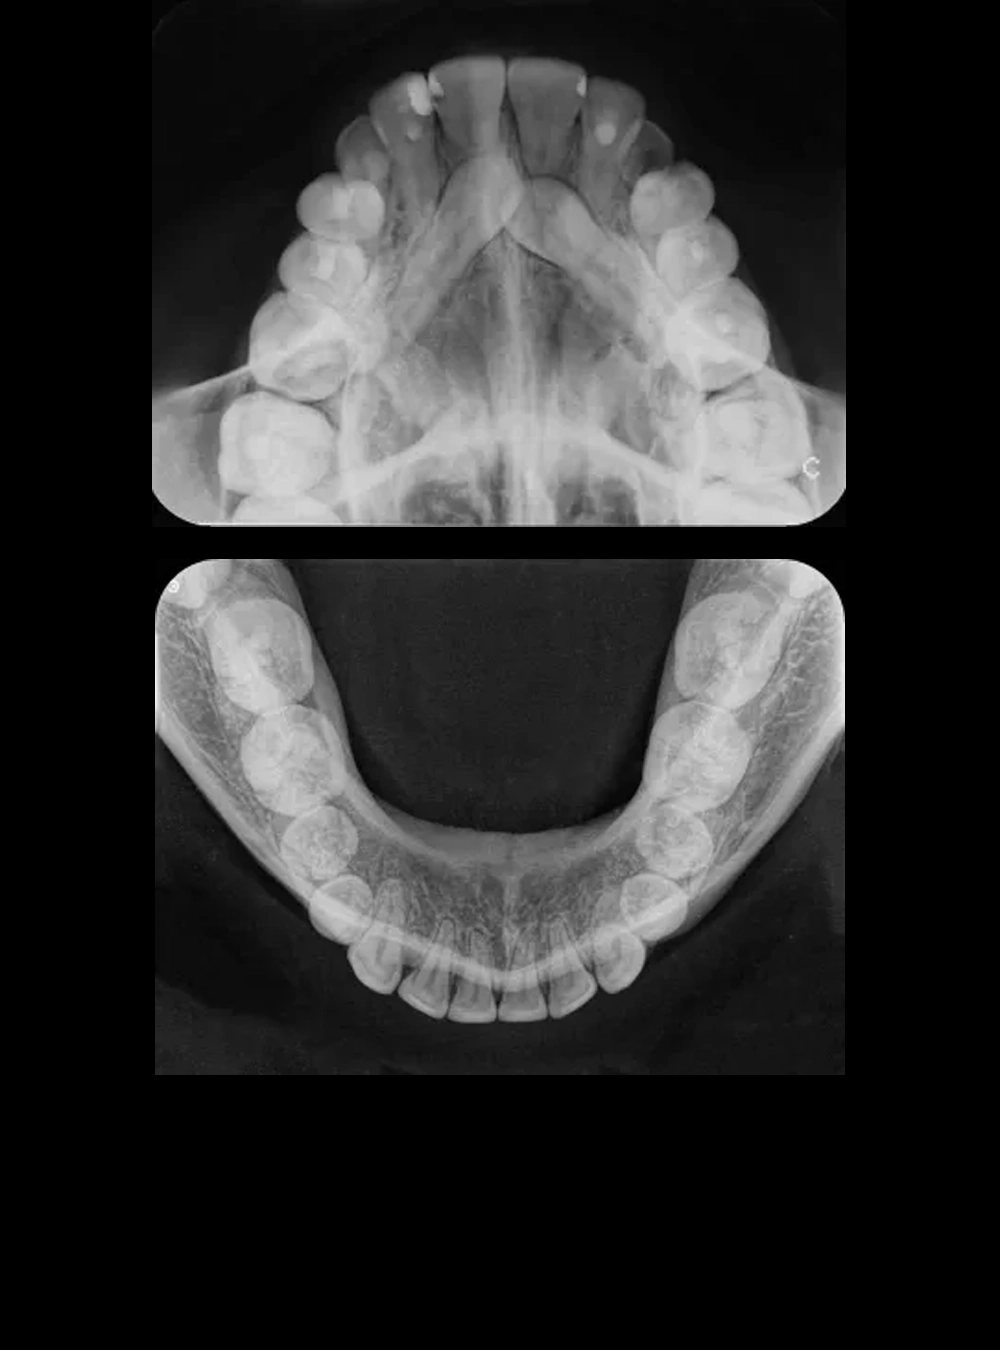

Rx Oclusal Superior e Inferior

• Oclusal Superior

• Oclusal Inferior